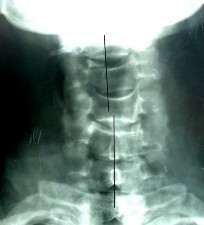

SAU CHẤN THƯƠNG: TRẬT 1 MỎM KHỚP C4 – C5

THẲNG NGHIÊNG

Đường liên gai mất liên tục Bán trật xoay C4-C5

BÁN TRẬT MỎM KHỚP C4-C5 (P) TRẬT MỎM KHỚP C4-C5 T